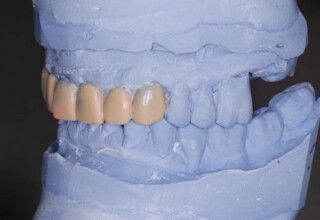

Οι όψεις πορσελάνης είναι ο καλύτερος τρόπος αντιμετώπισης αισθητικών προβλημάτων στην πρόσθια περιοχή του στόματος. Συνδυάζουν συντηρητική αφαίρεση οδοντικής ουσίας και πολύ υψηλή αισθητική απόδοση. Στο παρακάτω εκτεταμένο περιστατικό υπήρχαν: παλαιά σφραγίσματα, δυσχρωμίες, κακό σχήμα και μήκος δοντιών, κακή αναλογία δοντιών-ούλων. Έγινε προσεκτικός εργαστηριακός σχεδιασμός σε εκμαγεία απ’όπου προέκυψαν προσωρινές όψεις που τοποθετήθηκαν στο στόμα για δοκιμή και διορθώσεις. Όταν οριστικοποιήθηκαν οι μετατροπές, οι προσωρινές χρησιμοποιήθηκαν σαν οδηγός για τις μόνιμες. Οι πέντε μόνιμες όψεις πορσελάνης που κατασκευάστηκαν για τα πέντε πρόσθια δόντια της άνω απεκατέστησαν σχεδόν άψογα την αισθητική εμφάνιση της ασθενούς.

Εκτεταμένη αποκατάσταση με στεφάνες(θήκες) σχεδόν σε όλα τα δόντια λόγω εκτεταμένων αποτριβών, παλαιών αποκαταστάσεων, οπισθίων απονευρώσεων και αισθητικών προβλημάτων. Ο ασθενής(60 ετών) παρουσίαζε έντονο βρυγμό (τρίξιμο δοντιών) που δεν είχε αντιμετωπίσει ποτέ, με αποτέλεσμα μεγάλες αποτριβές που απειλούσαν την ακεραιότητα των οπισθίων δοντιών. Οι ανασυστάσεις(σφραγίσματα) των δοντιών έγιναν κυρίως με συγκολλούμενα ρητινώδη υλικά και τρεις χυτούς άξονες ψευδοκολοβώματα. Τοποθετήθηκαν προσωρινές στεφάνες όπου εκτιμήθηκε το επιθυμητό μέγεθος, το σχήμα και η θέση των δοντιών πριν κατασκευαστούν οι τελικές μόνιμες στεφάνες.

Χρησιμοποιήθηκαν παλαιές χαμογελαστές φωτογραφίες της ασθενούς γιατί είχε χαθεί τελείως το φυσικό σχήμα των δοντιών εξαιτίας των πολλαπλών προσθετικών προσπαθειών που είχαν γίνει στο παρελθόν. Μεταφέρθηκε στην προσωρινή γέφυρα η σχέση των φυσικών δοντιών μεταξύ τους άλλα και με τα χείλη. Δοκιμάστηκε η φώνηση και η μάσηση με δυο διαφορετικές προσωρινές άνω γέφυρες και εκτιμήθηκε η αισθητική απόδοση τους. Αφού επιτεύχθηκαν σε βαθμό ικανοποιητικό η φώνηση και η αισθητική εμφάνιση της οδοντοφυΐας, η προσωρινή αποκατάσταση χρησιμοποιήθηκε ως οδηγός για την τελική.